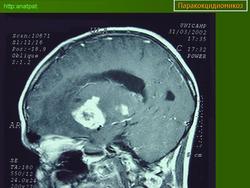

ГМ. Паракокцидиомикоз. +

Паракокцидиомикоз.

Множественные "узловые образования" имитирующие метастазы.